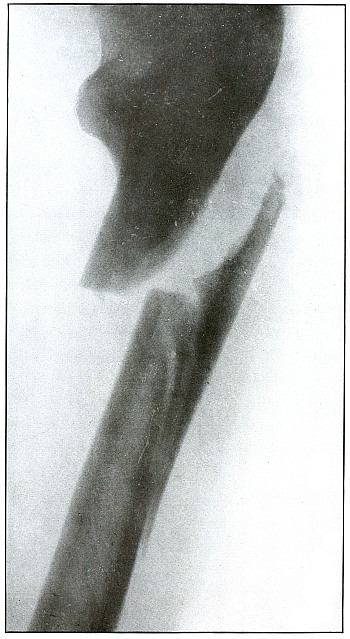

Gunshot fracture, femur |

114 |

| 53. |

Gunshot fracture, femur |